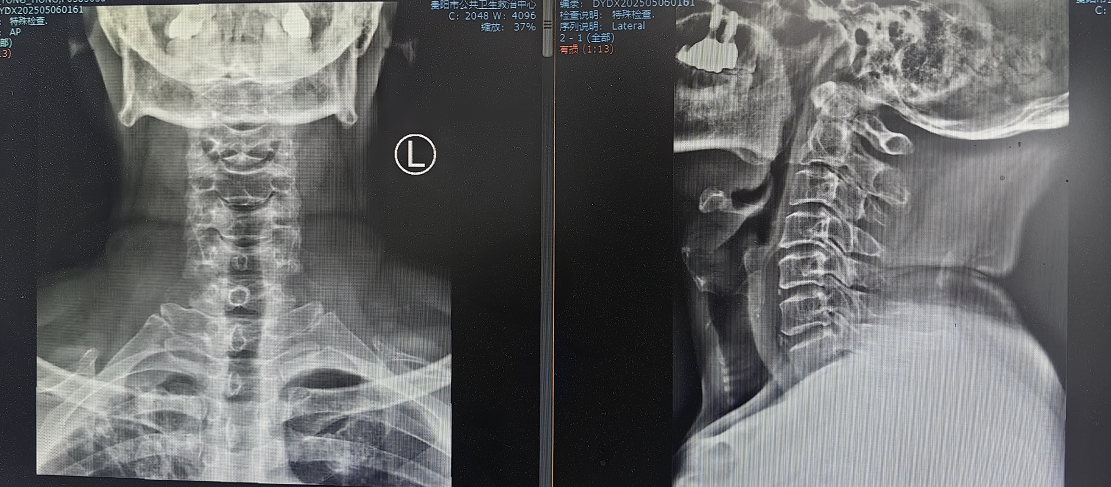

患者因"頭痛、雙上肢麻木伴下肢乏力1月"入院,此前長期保守治療效果不佳,癥狀持續(xù)加重并出現(xiàn)行走不穩(wěn)。經(jīng)多學科聯(lián)合會診,團隊決定采用國際先進的零切跡cage融合術。手術歷時2小時,出血量僅10ml,術后患者即刻感到頸部及肢體癥狀顯著緩解,術后三天即可下床活動,微創(chuàng)切口(3—4厘米)及快速康復效果獲家屬高度贊譽。